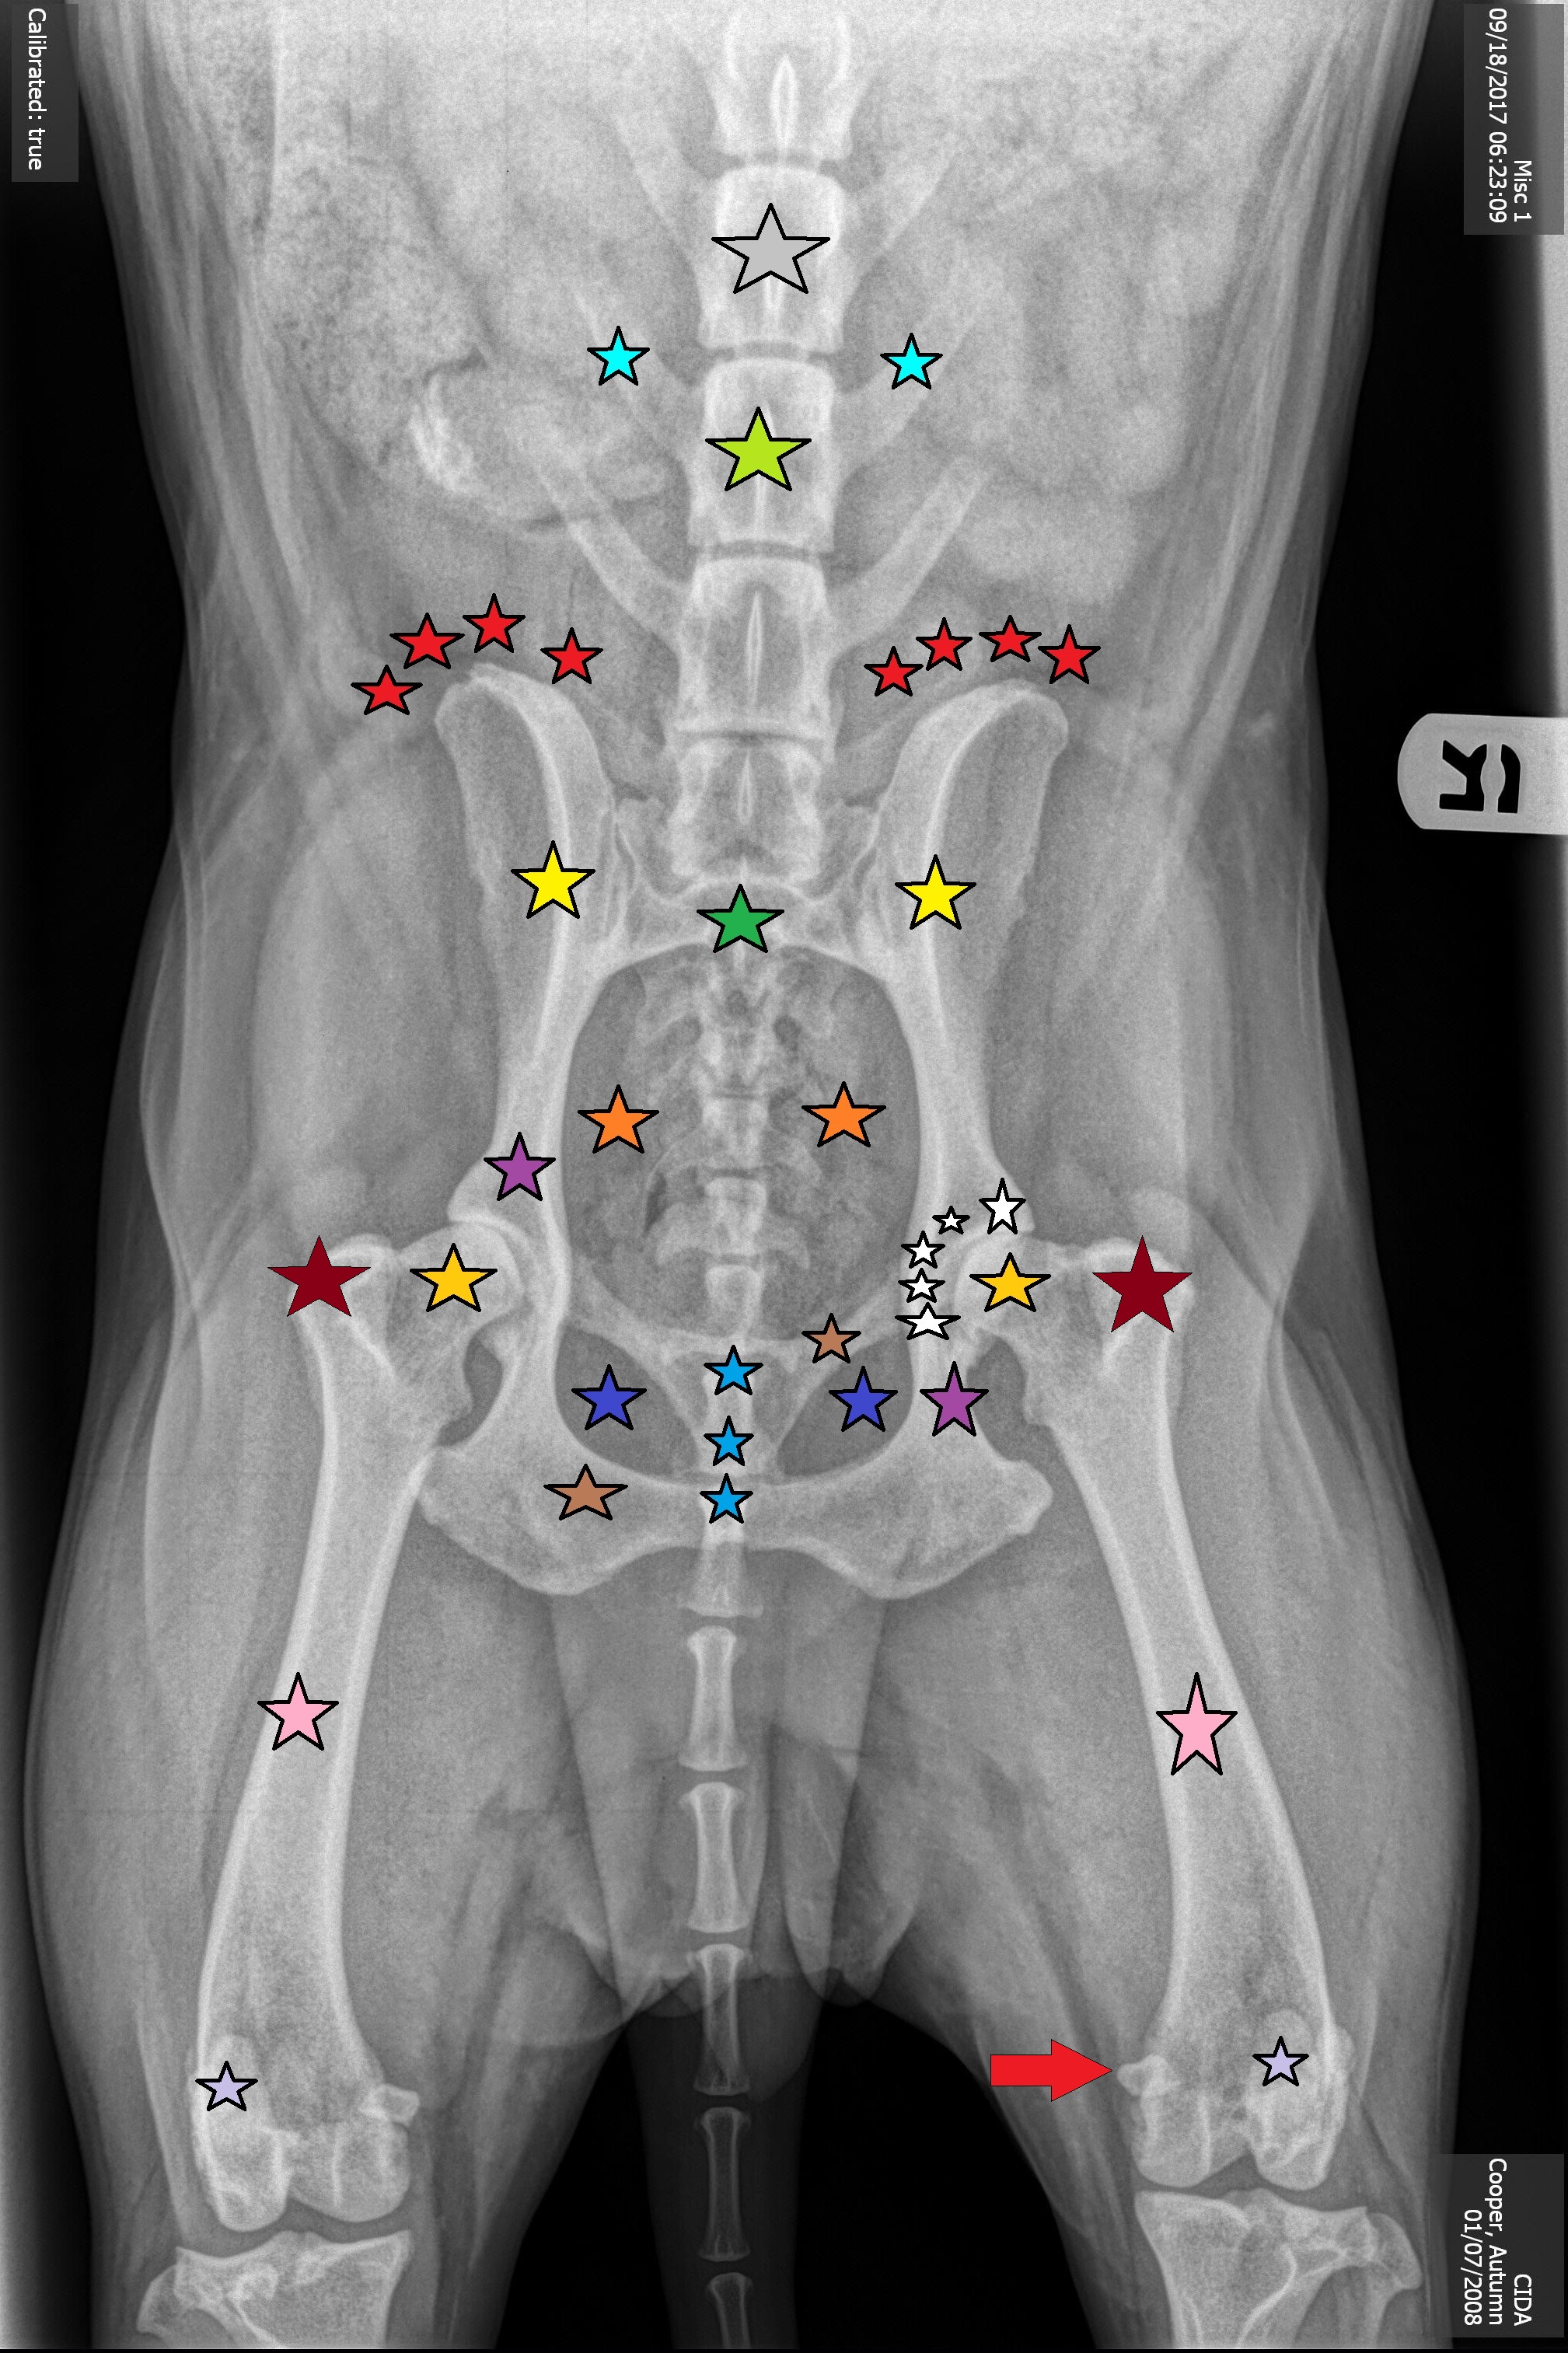

Gray Star

Lumbar Vertebrae #4, L4

Bright Blue Stars

Transverse Processes of L5

Neon Green Star

Lumbar Vertebrae #5, L5

Red Stars

Wings of Ilium

Yellow stars

ilium

Green Star

Sacrum

Orange Stars

Pelvic Outlet

Dark Purple Stars

Ischium

Dark Blue Stars

Obturator Foramen

Blue Stars

Pubic Symphysis

Brown Stars

Pubis Bone

Gold Stars

Head of the Femur

Maroon Stars

Greater Trochanter

White Stars

Acetabulum

Pink Stars

Femur Bone

Light Purple Stars

Patella Bone